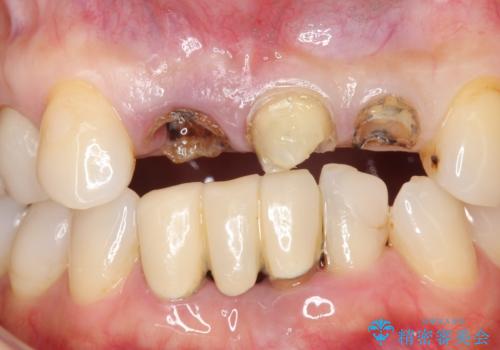

- 下顎前歯部の突き上げで上顎前歯の被せ物が土台ごと外れてしまった方の症例です。

右上1番目の歯は根元まで割れてしまっており、保存不可能だったため抜歯となりました。

抜歯後、骨と歯肉の回復を待ち、オールセラミッククラウンによるブリッジで補綴を行いました。

今回用いたオールセラミッククラウンはジルコニアフレームという白い素材の上にセラミックを盛っているため、審美性が非常に高いのが特徴です。

また、ジルコニアは人工ダイヤモンドの材料にも使われているほど高い強度を持っており、そのためオールセラミッククラウンは審美性だけでなく、奥歯やブリッジの補綴も可能とするクラウンです。